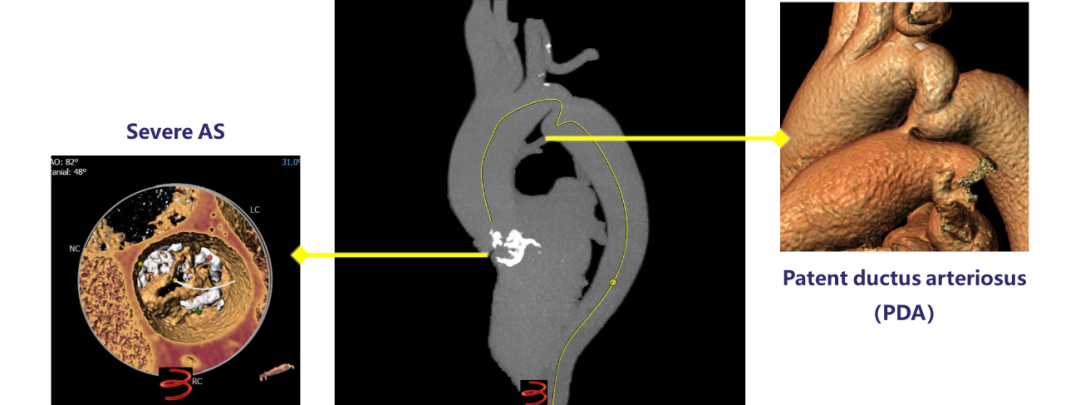

近日,吉林大学第二医院刘斌主任、张春鹏教授带领TAVR团队,成功实施一站式TC-TAVR+PDA封堵手术,成功救治一位重度主动脉瓣狭窄合并主动脉缩窄、动脉导管未闭的患者,该一站式手术为东北首例。

患者女性,58岁,颜面部水肿4年余,活动后气促1年余,加重半月,伴双下肢间歇性水肿,未予以系统诊治,近半月来,患者自感上述症状较前加重,伴夜间阵发性呼吸困难,为求进一步诊治,遂来我院,门诊以“心力衰竭”收住我科。入院查体:心率:70次/分,主动脉第一及第二听诊区均可闻及2/6收缩期吹风样杂音及舒张早期杂音,双下肢水肿;血压:112/70 mmHG,初步诊断患有缺血性心肌病:不稳定性心绞痛,心功能Ⅳ级;低血钠症。心脏彩超:主动脉瓣钙化,主动脉瓣狭窄(重度)兼关闭不全(重度):Vmax 473 cm/s,PGmean 49 mmHG,PGmax 90 mmHG;升主动脉轻宽,全心增大,左室后壁增厚,左心功能减低,三尖瓣中度反流,二尖瓣轻度反流,肺动脉高压(轻度):SPAP 49 mmHG,EF 36%。

主动脉缩窄多为先天发育异常导致的,手术治疗的最佳年龄是6-16岁,由于成人后血管脆性增加,手术较为困难,故此次术中未进行干预,术后测量上肢血压:132/77 mmHG,下肢血压:177/95 mmHG,提示患者主动脉缩窄并未影响血流动力学;PDA封堵器位置良好,未见残余分流;人工主动脉瓣膜位置形态良好,跨瓣压差由49 mmHG降至8 mmHG,微量瓣周漏;手术取得圆满成功。